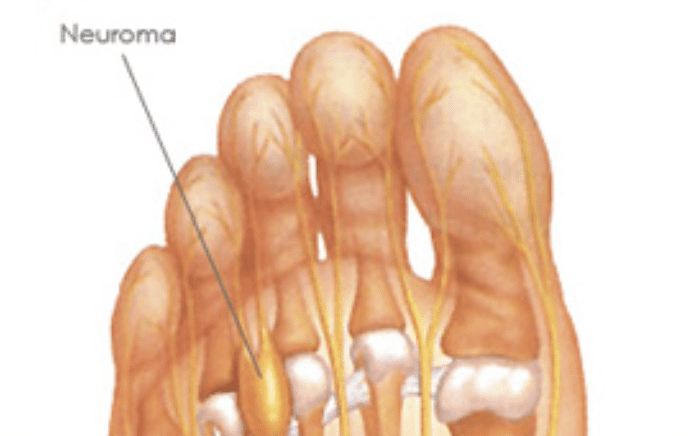

Common Foot & Ankle Disorders

Did you know the foot has 26 bones, 33 joints, 107 ligaments, 19 muscles, and numerous tendons? These parts all work together to allow the foot to move in a variety of ways while balancing your weight and propelling you forward or backward on even or uneven surfaces. It is no wonder that 75 percent of all Americans will experience foot problems at one point or another in their lifetimes.